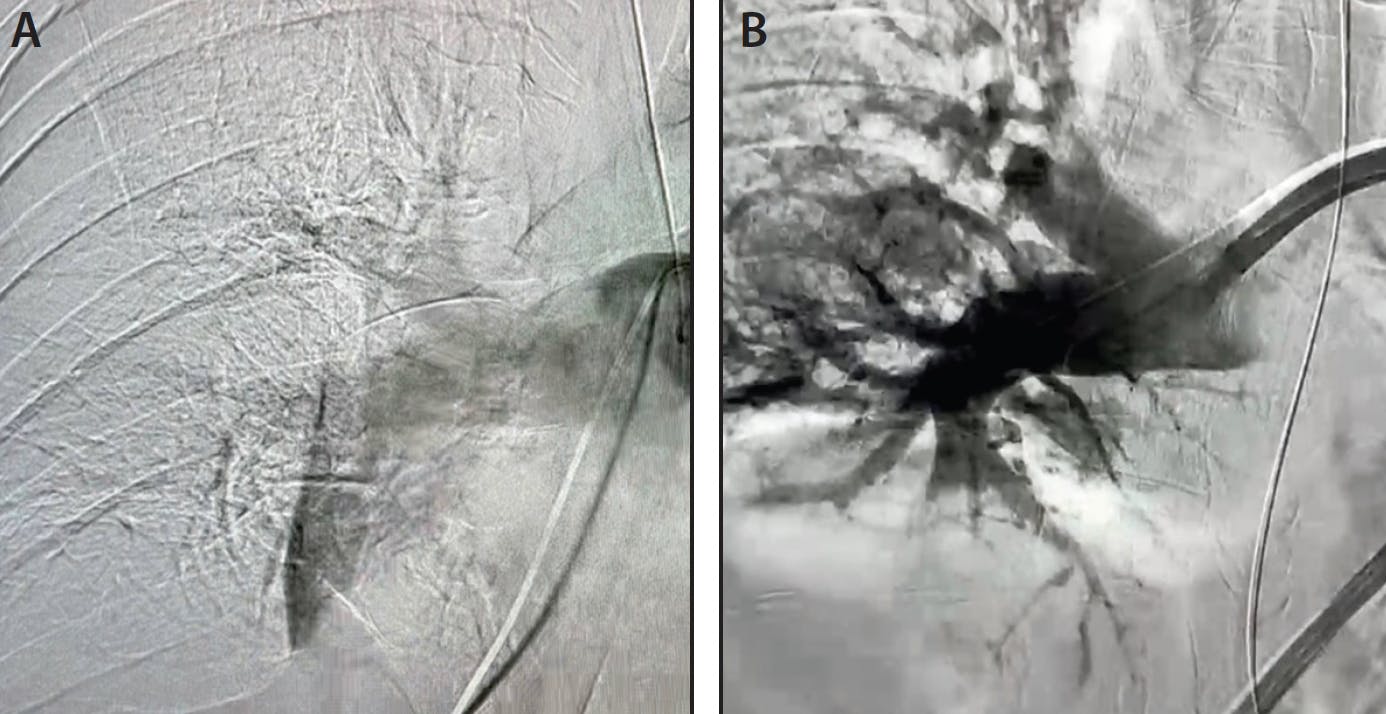

Preprocedural venograms confirmed extensive thrombus in the right iliac vein and IVC with evidence of IVC filter–related thrombosis (Figure 1A). Access was gained in the right popliteal vein with an 11-F Pinnacle sheath (Terumo Interventional Systems). Initially, a Lightning 12 was pulled and advanced into the iliac system. After four passes, a significant amount of clot was extracted from the iliac system, and flow was restored (Figure 2A). Focus was then shifted to removing the residual thrombus located in the IVC. At this point, Lightning Flash was selected to treat the IVC. In only two passes, Lightning Flash was able to aspirate both the in-filter and IVC clot with only 50-mL blood loss (Figure 1B). The clot removed was clearly organized in nature, which made thrombectomy with Lightning Flash more impressive (Figure 2B).

Figure 1. Preprocedural venogram showing thrombus present in the IVC and IVC filter (A). Final venogram showing thrombus removal (B).

Figure 2. Clot extracted after four passes with the Lightning 12 (A). Organized clot extracted after two passes with the Lightning Flash (B).